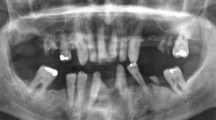

WEANLING rabbits given single injections of 500–1,000 µc. strontium-90 per kgm. showed a high frequency of tumours of the jaw1, and preliminary histological studies suggest that they arose in close relation to the teeth. The amount of strontium-90 accumulated in individual teeth and in all teeth of one upper quadrant of the jaw after a single intravenous injection of 100 µc. strontium-90 per kgm. is given in Table 1. The amount of strontium-90 in the teeth is seen to increase with time after injection for at least thirty days and then to fall abruptly. The teeth of the rabbit grow continuously, and strontium-90 is lost because the layers in which the strontium is initially deposited erupt into occlusion and are later worn away in mastication. A similar sudden loss of strontium-90 from the teeth of the rat may be seen autoradiographically2.